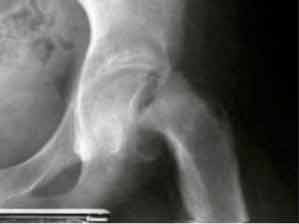

Epiphysen Lösung mit einem Abrutschwinkel von über 40°.